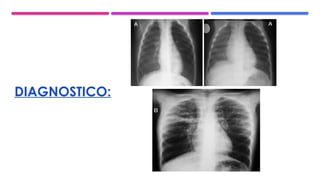

DIAGNOSTICO: